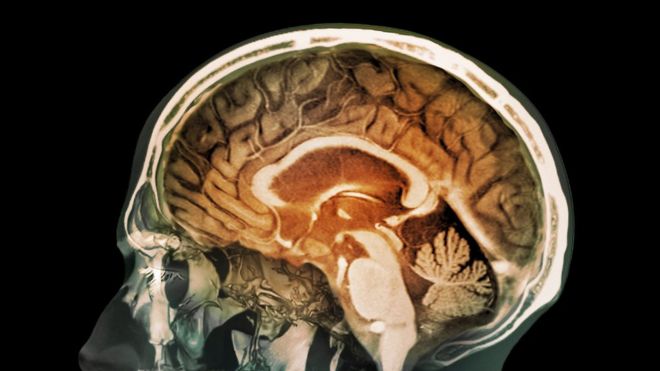

Es la primera vez que se encuentra evidencia de que partículas de la contaminación pueden llegar al cerebro. ZEPHYR/SCIENCE PHOTO LIBRARY